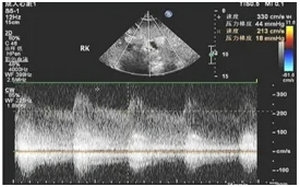

▲ 频谱:右肾动脉中段流速显著加快

1.定位:右侧肾动脉中段

2.定性:肾动脉纤维肌发育不良

3.定量:重度狭窄